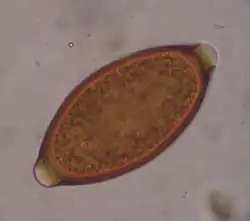

Trichuris trichiura, ou Trichocephalus trichiuris, est une espèce de nématodes (les nématodes sont un embranchement de vers non segmentés, recouverts d'une épaisse cuticule et menant une vie libre ou parasitaire). C'est l'un des parasites du tube digestif humain, dont des œufs fossilisés sont encore trouvés sur des lieux de fouilles archéologiques préhistoriques[1].

C’est un nématode de 3 à 5 cm de long.

Ce parasite peut être mis en évidence par un examen parasitologique des selles chez le sujet infesté.